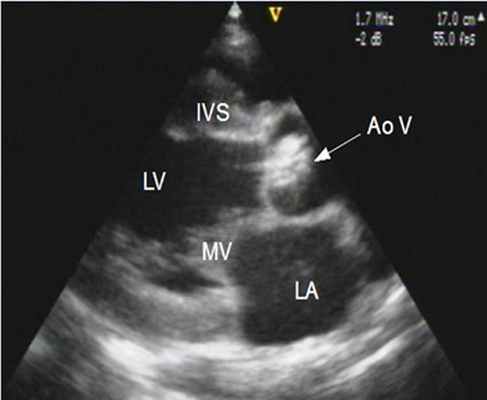

Видео. Врожденный аортальный стеноз при ЭхоКГ вдоль длинной оси выводного тракта левого желудочка из парастернальной позиции датчика. Отчетливо видно неполное систолическое движение створки аортального клапана при его раскрытии с куполообразным выпячиванием (стрелка).

3. Двумерная эхокардиография. Морфологические изменения аортального клапана у взрослых наиболее отчетливо видны при многопроекционной ЧПЭ. Иногда при этом исследовании удается непосредственно измерить площадь клапанного отверстия. Нередко отмечается смещение открытия правой коронарной створки, которая может пролабировать в диастолу в выносящий тракт левого желудочка. На видеозаписи выше видны асимметрия аортального клапана, систолическое выбухание и диастолическое пролабирование в выносящий тракт левого желудочка. Субаортальная область левого желудочка, как правило, широкая, но при выраженном стенозе аортального клапана может оказаться стенозированной из-за развития гипертрофии межжелудочковой перегородки.

В восходящем отделе аорты, особенно при легком и умеренном стенозе аортального клапана, отмечается постстенотическое расширение.